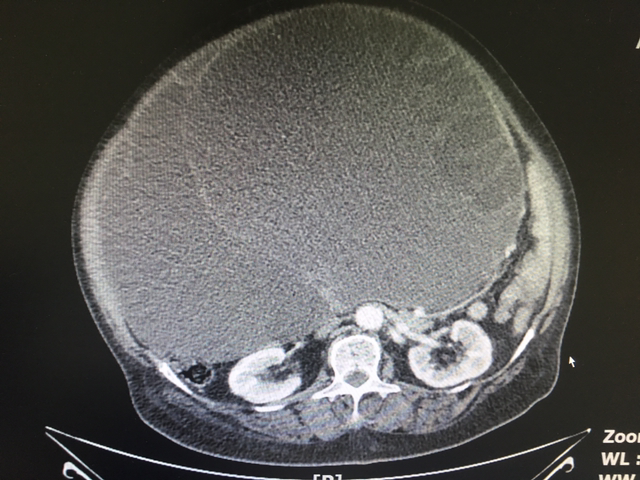

73세 영자 할머니. 숨이 차시다며 응급실을 찾으셨다. 관절에 좋다는 마가목 껍질을 우려먹은 뒤 복부팽만이 심해지셨단다. Drug intoxication 의심 하에 검사를 진행했는데 결과는 뜻밖이었다.

복부 CT에서 ovarian mucinous cystadenocarcinoma가 발견됐다. 물증에 입각해 추가 문진. 일 년 전부터 월경이 재개돼 이상하게 여기셨다고. 아내 통해 모교병원 산부인과에 환자 상태 알리고 추가적 처치를 받도록 연결했다.